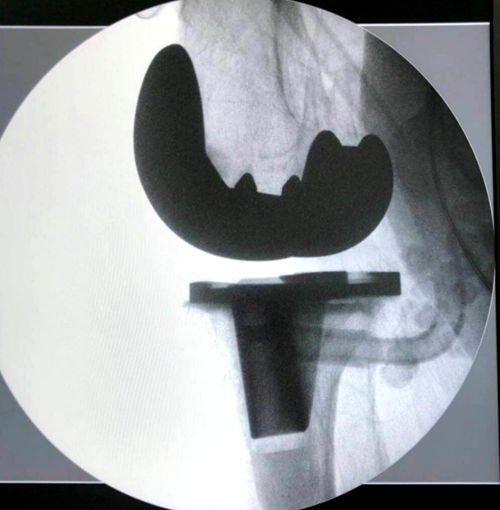

5月14日,湘雅常德医院骨科专家团队为王阿姨成功实施了左膝关节置换术,手术过程顺利、流畅、精细。术后为王阿姨制定了专门的康复训练方案,王阿姨在骨科全体医务人员周到细致的护理下,术后恢复良好,并于5月28日顺利拆线出院。

膝关节置换手术是骨科的一项大手术,对手术医生的技术要求非常高,对骨关节炎治疗具有非常好的疗效,是治疗膝骨性关节炎的最终治疗手段,能使老年患者免于病残,恢复生活自理能力。